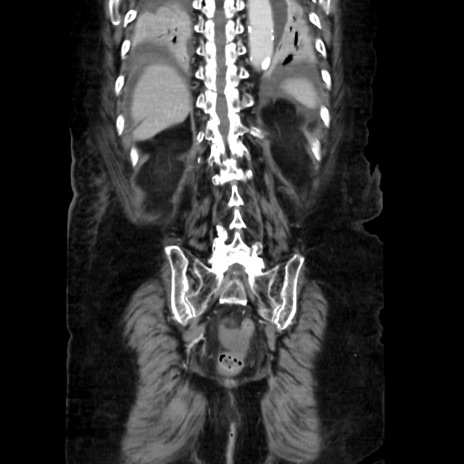

症例40(冠状断像)

【症例】90歳代女性

【主訴】腹痛・嘔吐

【現病歴】 食欲低下、嘔吐があり昨日他院受診。肺炎と診断され入院となる。入院後より腹部全体に圧痛あり。胃管留置され経過みていたが、症状持続するため、

当院転院となる。

【既往歴】胸椎圧迫骨折、胆石症

【身体所見】腹部:中央に激痛あり、圧痛あり、反跳痛不明

【データ】WBC 17100、CRP 18.82

矢状断像